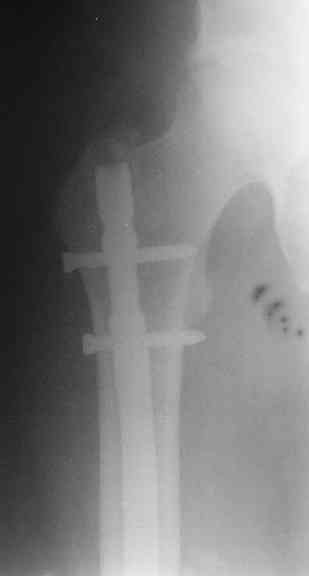

Если имеете доступ к trochanteric медуллярным штифтам TAN Smith Nephew или DePuy, где имеется offset на 8 градусов для удобства черезвертельного введения и профилактики нарушения кровеснабжения

головки (см. снимок) можно было применить штифт, в котором опороспособность достигается за счет блокирующих шурупов сверху и снизу.

На сегодня редко используются прямые piriformis штифты для антеградного введения. И универсальный Versanail от DePuy, выпускаемый для ретро-и антеградного применения с различными вариантами блокировки, в основном применяется для ретроградного введения.

Учитывая, что ложный сустав с укорочением, для восстановления необходимо применение дистракции (на кольцах или femoral distractor) или другой методикой, например после определения длины, штифт вводят в канал, не снимая Insertion tool, блокируется дистально шурупами и дальше штифт доводится до желаемого положения, затем через jig

производят блокировку проксимально

Костная масса, полученная в результате рассверливания канала, кстати, прекрасный пластический материал, можно использовать для лечения ложного сустава. Через любую трубку небольшого диаметра, без открытия фокуса, можно уложить на место дефекта. Блокирующие шурупы в 6.5 и 5.0 мм диаметра, и больной смело может передвигаться, потому что 12 мм штифт с одним дистальным и проксимальным блокирующими шурупами выдерживает вес в 75 кг.